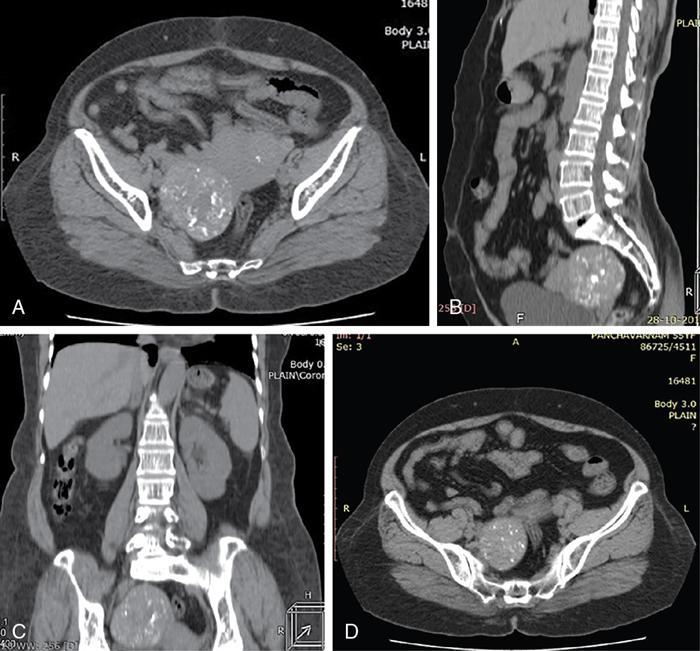

John De Lindsay, Sumathy, Vasumathy, Usha nandhini Ganeshan, N. Sundari ENDOMETRITIS Endometritis is defined as the inflammation of the uterine endometrial layer. Endometritis is frequently observed in the pregnant and postpartum population. Pelvic inflammatory disease (PID) and invasive gynaecological procedures are the most common causes of acute endometritis in nonobstetric population. Endometritis is the most complex asymptomatic and often presents with subclinical form of PID. Ultrasound may reveal minimal particulate endometrial fluid with mildly thickened endometrium showing increased vascularity. Computed tomography (CT) findings include a diffusely bulky uterus due by inflammation, mild fluid distension of endometrial cavity and striking endometrial enhancement in comparison to the adjacent myometrium due to mucosal hyperaemia. ‘Indistinct uterine border’ sign is observed in patients with endometritis, which is defined as the loss of distinction between the uterus and the adnexa. Since it is also observed in the cases of endometriosis or malignancy, it is a nonspecific sign. The age of the patient, clinical presentation, and the biopsy of endometrium helps in differentiating endometritis from other pathologies. UTERINE ARTERIOVENOUS MALFORMATION Uterine arteriovenous malformation (UAVM) is an abnormal connection between the arteries and the veins of the uterine myometrium without an intervening capillary bed. They were first reported by Dubreil and Loubat in 1926. They can be congenital or acquired. Even though UAVMs have varied presentation, uterine bleeding is the most common one. They often follow a pregnancy event. Episodic or occasionally torrential vaginal bleeding can occur. Congestive heart failure secondary to vascular steal can be a rare presentation due to a large UAVM. UAVM is most commonly an acquired condition. Pregnancy has a significant role in their pathogenesis. It is most commonly observed in reproductive age group. UAVMs are frequently observed in the postpartum period, few months after spontaneous miscarriage, surgical evacuation of uterus for miscarriage or medical termination of pregnancy. Infection, inflammation, retained products of conception (RPOC), gestational trophoblastic disease (GTD), gynaecologic malignancies, pelvic trauma and exposure to diethylstilboestrol can also lead to UAVMs. Few cases are also reported in young adolescent and postmenopausal females. UAVMs rarely are congenital and may be also associated with AVMs in other locations. Congenital AVMs Congenital AVMs have a central nidus with multiple feeding arteries and draining veins. In this condition, there is extension of the lesion beyond that uterus and multiple pelvic vessels other than uterine vessels draining into them. That cause of congenital AVMs are thought to be due to failure of embryological differentiation. With the progression of pregnancy, these vessels have the propensity to invade surrounding structures. Iatrogenic Acquired AVMs When the venous sinuses are incorporated into the scars of myometrium after the necrosis of chorionic villi, acquired malformations may arise. In contradiction to congenital AVMs, acquired AVMs multiple fistulous communication between the intramural arteries and the venous plexus. These AVMs may have either dual blood supply or a single supply from the uterine arteries and presents without nidus. Vaginal bleeding caused by pregnancy-related causes must be differentiated from UAVMs. Surgery/evacuation is the appropriate management for the former and the same is contraindicated in the UAVMs and hence an accurate definitive diagnosis is important. Grey-scale ultrasound findings are nonspecific and they are subtle heterogeneity of myometrium with multiple tubular or ‘spongy’ anechoic or hypoechoic areas. In spite of varied presentations such as an intramural uterine, endometrial or cervical mass-like lesions or prominent parametrial vessels, it has minimal mass effect. On colour Doppler, within the myometrium, a region of increased vascularity and most commonly with aliasing is seen. A group of vessels traversing the myometrium running perpendicular to and into the endometrium, from the arcuate vessels, can be seen. It is not specific, as they are also observed in RPOC, GTD, placental polyp and vascular endometrial neoplasm. In pulsed Doppler, multidirectional turbulent flow with intense vascularity can be seen with high peak velocity (mean peak systolic velocity [PSV] = 136 cm/s) and low resistance (mean resistance index = 0.3) flow. The arteries have low pulsatility while the draining veins are pulsatile and show high velocity flow. Magnetic resonance imaging (MRI) offers noninvasive confirmation of the diagnosis of UAVM. T1-weighted and T2-weighted images show multiple serpentine signal voids along the uterine wall, endometrial cavity and parametrium. Contrast-enhanced MR angiography shows intensely enhancing complex serpentine abnormal vessels with early venous return. Catheter angiography can be reserved only for women who require embolization of the AVM. The consent for both diagnostic angiography and therapeutic embolization should be obtained simultaneously to avoid repeat therapeutic procedures. Management of UAVM depends on: UAVM can be treated with medical therapy with hormones, uterine artery embolization or with definitive hysterectomy. Once the diagnosis of a UAVM is confirmed, the treatment option depends on the clinical condition of the patient. The size of the AVM bears no correlation to the need for embolization. Timmerman et al. found that AVMs having PSV of at or above 0.83 m/s, most often requires embolization. Also, the vascular malformation with PSV value below 0.39 m/s does not require embolization. Placental bed subinvolution, enhanced myometrial vascularity (EMV), molar pregnancy or RPOC are the other causes of uterine mass vascular malformations which usually has a mean PSV of 0.52 m/s and does not require embolization. Transcatheter targeted uterine artery embolization is indicated in selected cases, if bleeding persists to a degree that blood transfusions are required to maintain haemodynamic stability or multiple repeated acute hospitalizations. This is preferred over surgical management owing to its immediate minimally invasive and fertility sparing benefits. Gelfoam had been suggested earlier as the material of choice for embolization. Various other embolic materials like polyvinyl alcohol, Histoacryl glue, stainless steel coils, detachable balloons, and haemostatic gelatin are also used nowadays. Normal intrauterine pregnancies after embolization have been reported, proving that an adequate collateral blood supply can develop to support a full-term pregnancy. Gestational Trophoblastic Disease RPOC: Presence of endometrial pathology rather than myometrial origin. FIBROIDS Leiomyomas, also known as fibroids or myomas, are the most common gynaecologic neoplasms, occurring in 20%–30% of women of reproductive age. Symptomatic uterine fibroid accounts for about 30% of hysterectomies performed for women older than 18 years of age and 41% of hysterectomies performed for women from 44 to 64 years of age. Leiomyomas are the benign neoplasms made up of whorled fascicles of smooth muscle and fibrous connective attached to the uterine muscular wall. Even in the absence of true capsule, leiomyomas are well circumscribed and contains a pseudocapsule. Its size is variable, ranging from tiny microscopic to large tumours filling the abdomen. Most commonly, the uterine leiomyomas are seen in the myometrium of uterine corpus. However, it is also seen in the cervix (<5% of cases). On the basis of the location, uterine fibroids are classified as submucosal, intramural or subserosal. This classification is of clinical significance because the symptoms and treatment vary among these subtypes of leiomyomas. Submucosal myomas are further subclassified as 0, I and II depending on the percentage within the endometrial cavity. The first two categories can be removed hysteroscopically (Table 11.15.3.1). Pedunculated leiomyomas are attached to the uterus by a stalk and may be either intracavitary or exophytic (narrower than 50% of diameter of myoma). Rarely, a submucosal fibroid may grow pedunculated and extends into the cervical canal or vaginal canal and its prevalence is about 2.5%. Pedunculated subserosal leiomyomas may undergo torsion, resulting in infarction accompanied by pain. Lateral growth into broad ligament leads to intraligamentous leiomyoma (Table 11.15.3.1). Rarely, a pedunculated leiomyoma may become detached from the uterus (parasitic leiomyoma). Depending on the location, size and number of uterine fibroids, it has varied presentation. Symptoms caused by leiomyomas are classified into three different categories such as abnormal uterine bleeding, pelvic pressure and pain and reproductive dysfunction. Submucosal leiomyomas and intramural leiomyomas are often associated with menorrhagia (Table 11.15.3.1). Because of leiomyoma, uterus may be irregularly shaped and causes symptoms based on their locations. Anterior leiomyomas cause urinary symptoms, whereas the posterior leiomyomas cause constipation. Ureter may be compressed by broad ligament leiomyomas and presents as hydroureter or hydronephrosis. In case of degeneration or torsion of a pedunculated leiomyoma, acute pain may be the presentation. Leiomyomas are an infrequent primary cause of infertility. Malpresentation, pregnancy failures and dystocia are reported. Ultrasound is the first-line imaging modality because it is a cost-effective portable real-time examination that provides good anatomic detail. Leiomyomas appear as a well-defined round or oval hypoechoic solid mass. It is mostly associated with posterior shadowing possibly due to calcifications or interface of the margins of the leiomyoma with the normal myometrium. Degeneration or lipoleiomyoma can be suggested when there is internal echo-poor or hyperechoic foci, respectively. The presence of hypervascularity in a large solitary uterine mass can identify suspicious masses, such as a leiomyosarcoma (LMS). Another study found that there is an increased detection rate of uterine sarcomas while using a cut-off value of 41 cm/s. In the assessment of a uterus enlarged with multiple leiomyomas, ultrasound has FOV limitations. Likewise, it has limited role in the assessment of retroverted uteri, pedunculated subserosal myomas and concomitant adnexal processes. Little has been reported regarding sonographic changes after MR HIFU and uterine fibroid embolization (UFE). Differential diagnosis has been discussed in Table 11.15.3.2. Hyperechoic unlike a myomatous polyp which appears hypoechoic Heterogeneous endometrium with little mass effect Enlarged uterus and a deformed contour are the most common computed tomography (CT) findings. Even though CT is the primary modality for the staging of cancers, it has limitation of reduced contrast resolution for the assessment of focal myometrial masses, and associated with risk of ionizing radiation. Also, in delineating the zonal anatomy for accurate localization of leiomyomas and LMSs, CT is inferior to magnetic resonance imaging (MRI). More often dense or amorphous calcification is seen. Almost exclusively, on plain radiography or CT, these patterns of calcification favours the diagnosis of leiomyoma. Ring-like calcification at the margins of a leiomyoma is a rarely observed pattern, which represents the thrombosed veins. Positron emission tomography (PET)/CT is an ideal modality for the confirmation of malignancy and also helps in detection of metastasis and recurrence. In a small study of patients with histopathologically confirmed uterine sarcoma found that on comparing with the findings of MRI and ultrasound with power Doppler imaging, the results of fluorodeoxyglucose (FDG) PET examinations were 100% positive. However, it has limitations such as increased false-positive rate and reduced widespread availability. MRI appearance of leiomyomas: MRI is considered as the most accurate imaging technique for the detection and localization of leiomyomas. In determining the presence and location of leiomyomas in infertile women before myomectomy, MRI has been shown to be more accurate and sensitive than US or hysterosalpingography. Nondegenerated uterine leiomyomas usually has a typical MRI appearance of (Table 11.15.3.4) well-circumscribed masses with homogeneously decreased T2-weighted signal intensity. TABLE 11.15.3.3 Note: SI, signal intensity; ADC, apparent diffusion coefficient. Compared with that of normal smooth muscle myometrium. Degenerated leiomyomas have varied imaging appearances on T1-weighted, T2-weighted and contrast-enhanced images as described in Tables 11.15.3.4 and 11.15.3.5. Hyaline Oedema *Common *50% cases *Usually peripheral Cystic Myxoid Carneous, red, or UAE associated Calcific Leiomyoma variants (Tables 11.15.3.4 and 11.15.3.6): There are several, such as mitotically active, cellular and atypical leiomyomas, as well as smooth muscle tumours of uncertain malignant potential (STUMP). On histopathological examination, the nondegenerated fibroids are made up of goals of uniform smooth muscles with varied amounts of collagen. Cellular leiomyomas, which are composed of compact smooth muscles cells only with no collagen, will demonstrate increased T2-weighted signal intensity and homogeneous enhancement. There is a greater risk of recurrence in case of atypical leiomyomas and uterine STUMP. The patients who had undergone myomectomy and were found to have atypical leiomyoma, must be under surveillance with an annual pelvic ultrasound or MRI. Since the recurrences may presents as pelvic or abdominal masses or as pulmonary metastases, for all the patients with STUMP lesions, routine physical examinations, including pelvic examinations and the baseline CT of the chest, abdomen and the pelvis are recommended for every 6 months for 5 years and then annually thereafter. In addition, prompt re-exploration and staging is recommended for patients with STUMP who have undergone a morcellation myomectomy. An aggressive imaging surveillance is considered, when the disease is present. Atypical leiomyomas and STUMPs routinely express progestin receptors; however, because of the low recurrence rates, there is no role for adjuvant hormonal therapy. Atypical uterine masses can be treated surgically with hysterectomy or myomectomy. Histologic subtype Cellular leiomyoma Round or oval Single large lesion with absence of coexistent adenomyosis Responds to GnRH analogues Cured with surgery No need for follow-up Lipoleiomyoma Well defined: round or oval STUMP Round or oval Intense surveillance Note: SI, signal intensity; ADC, apparent diffusion coefficient; UAE, uterine artery embolization; STUMP, smooth muscle tumours of uncertain malignant potential. Being a benign neoplasm, fibroids usually have a pushing border and rounded edges. But, specific types of fibroids represent growth pattern variations, such as intravenous leiomyomatosis, metastasizing leiomyoma, diffuse leiomyomatosis and peritoneal disseminated leiomyomatosis. Retroperitoneal growth and parasitic growth are the other atypical growth patterns. Even cervical and vaginal leiomyomas may show growth pattern. It is important to note that adenomyosis and focal myometrial contraction can coexist and distinction is important at preprocedure imaging (Table 11.15.3.7).